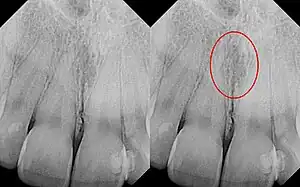

| Identical images with heart-shaped radiolucency highlighted in right film. | |

As a cyst, the nasopalatine duct cyst requires histological analysis for a definitive diagnosis. Radiographically, the nasopalatine cyst appears as a well-demarcated round, ovoid, or heart-shaped structure presenting in the midline of the maxilla.[6]